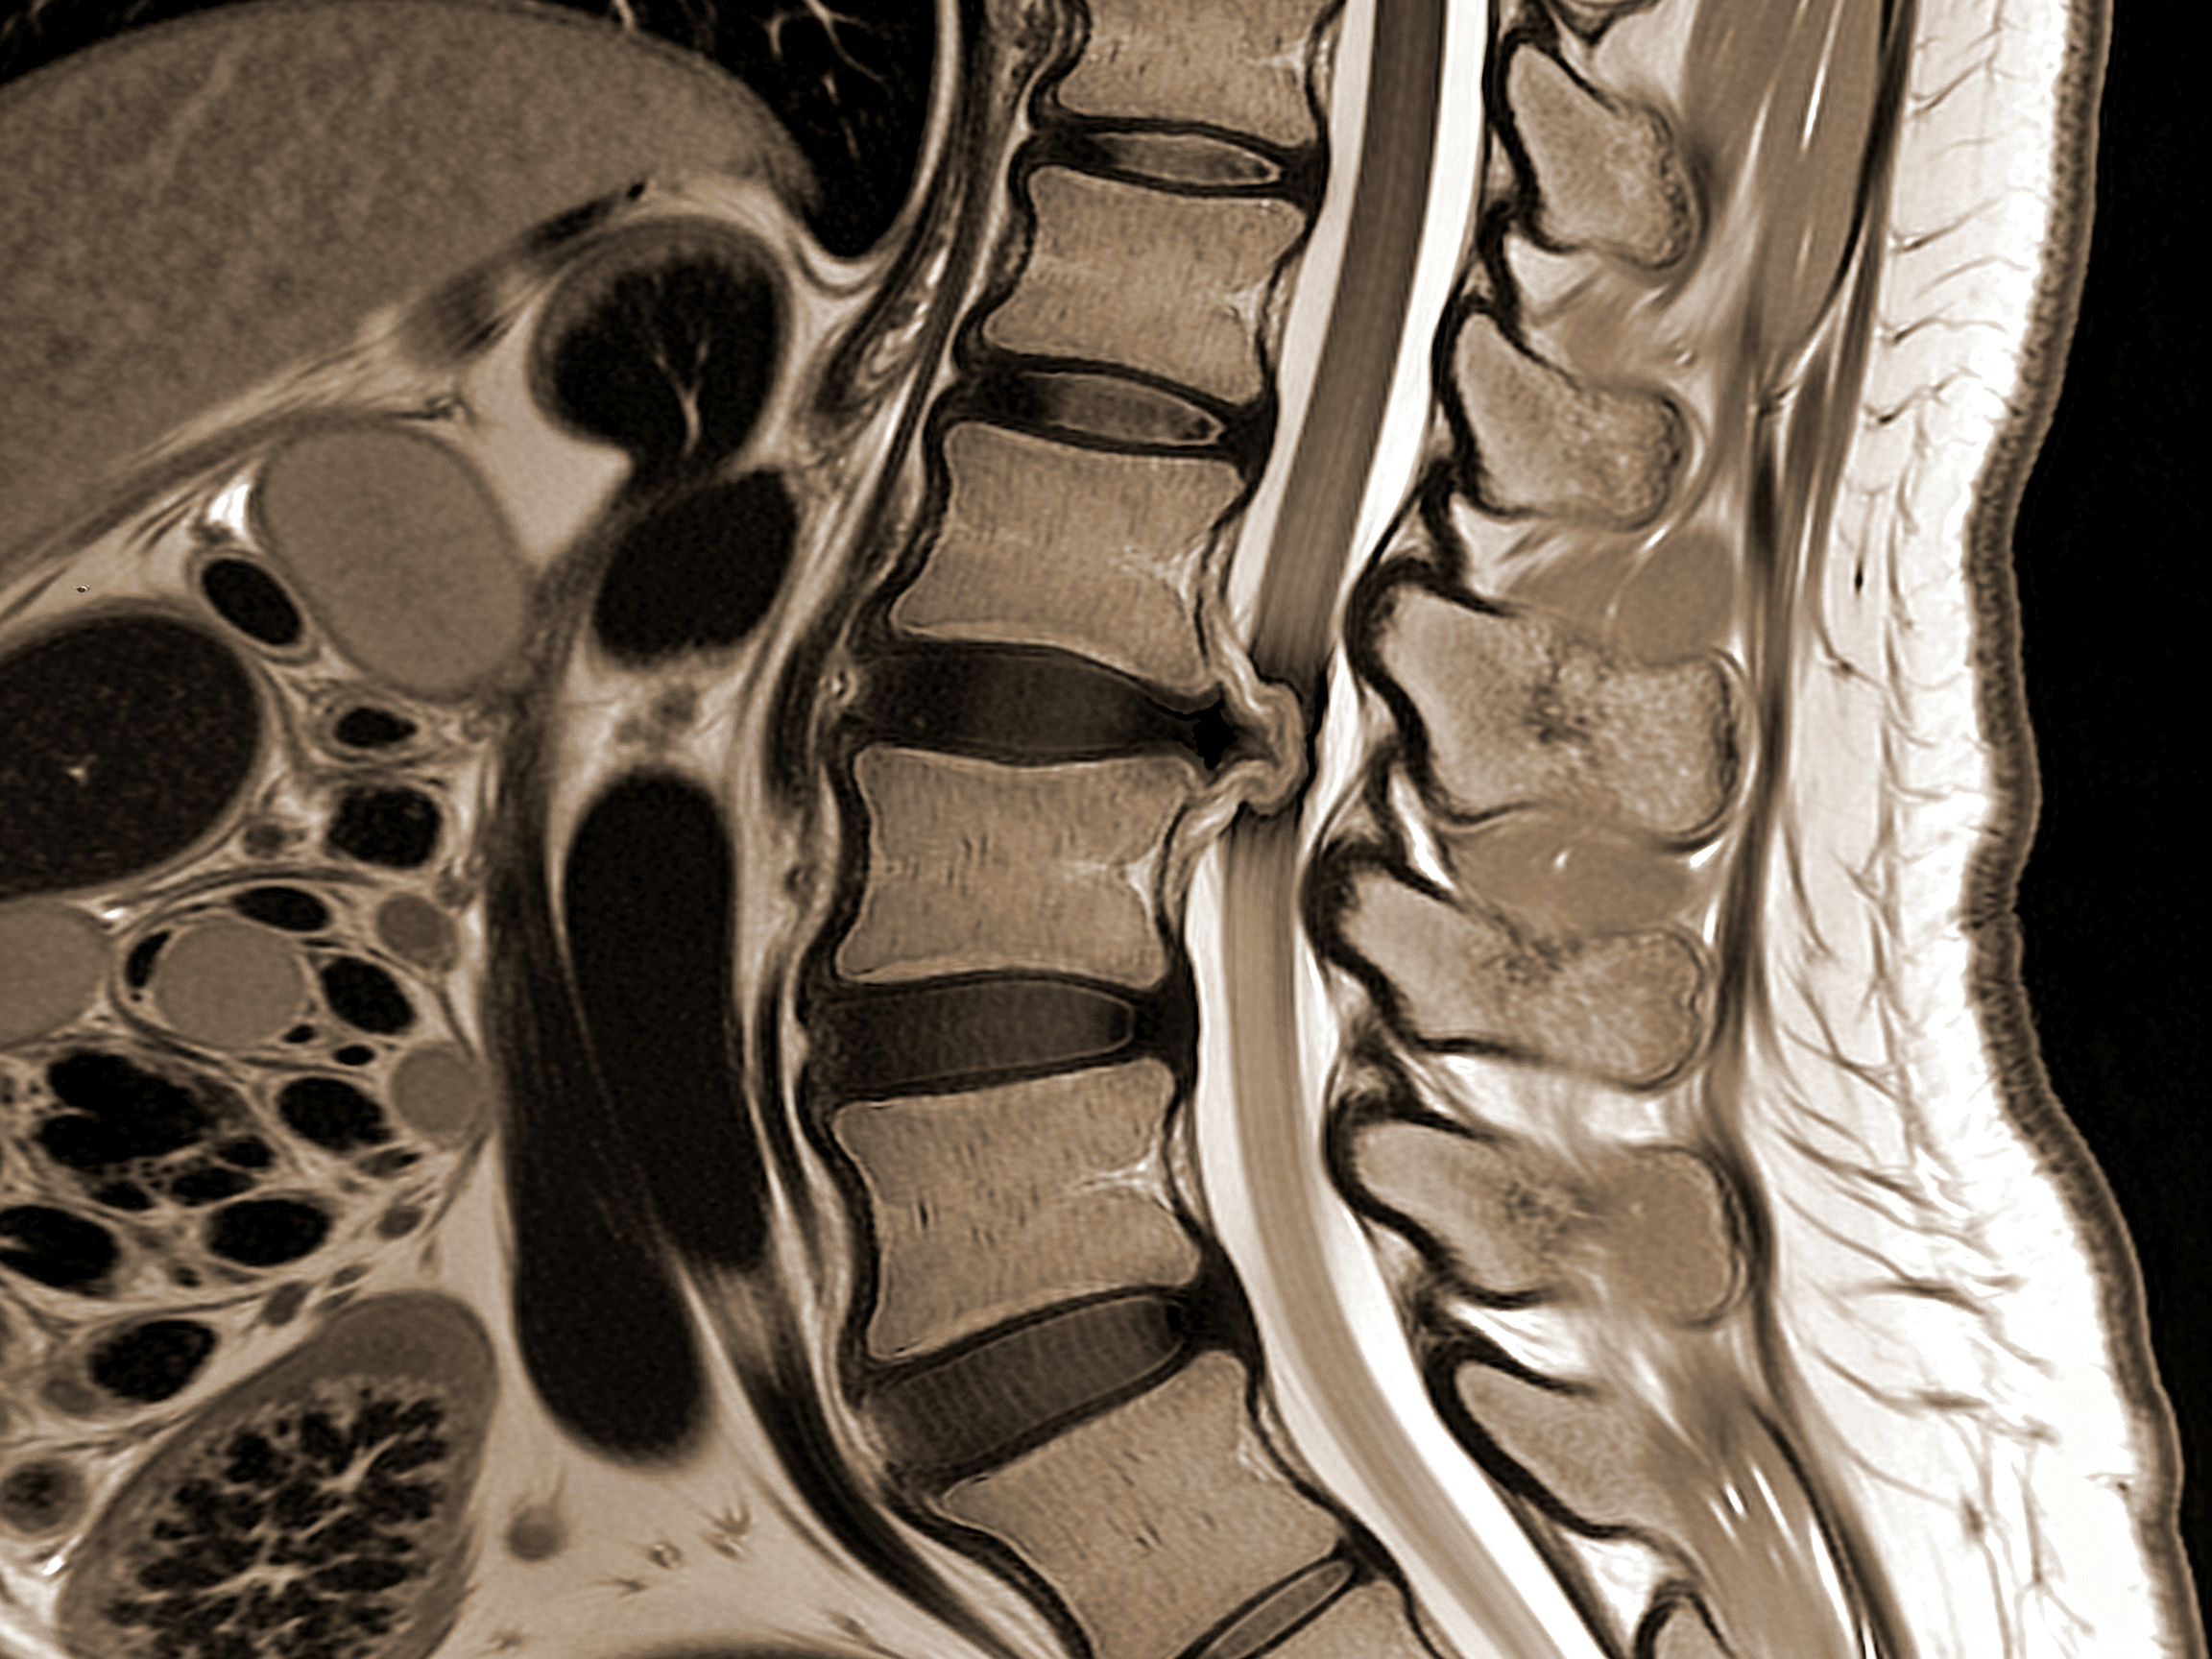

Emergency MRI spine coordination at Priority ER Odessa for spinal emergencies

State-of-the-art emergency MRI spine coordination available 24/7 at Priority ER